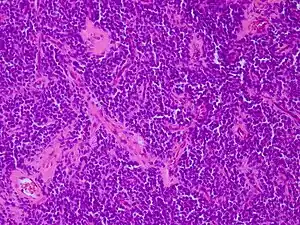

![]() | |

| Micrograph of an H&E stained section of a peripheral PNET. | |